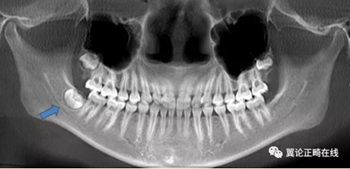

下頜智齒的存在還可能促進(jìn)下頜的生長(zhǎng),這是本病例難點(diǎn)之三。

拔除下頜智齒